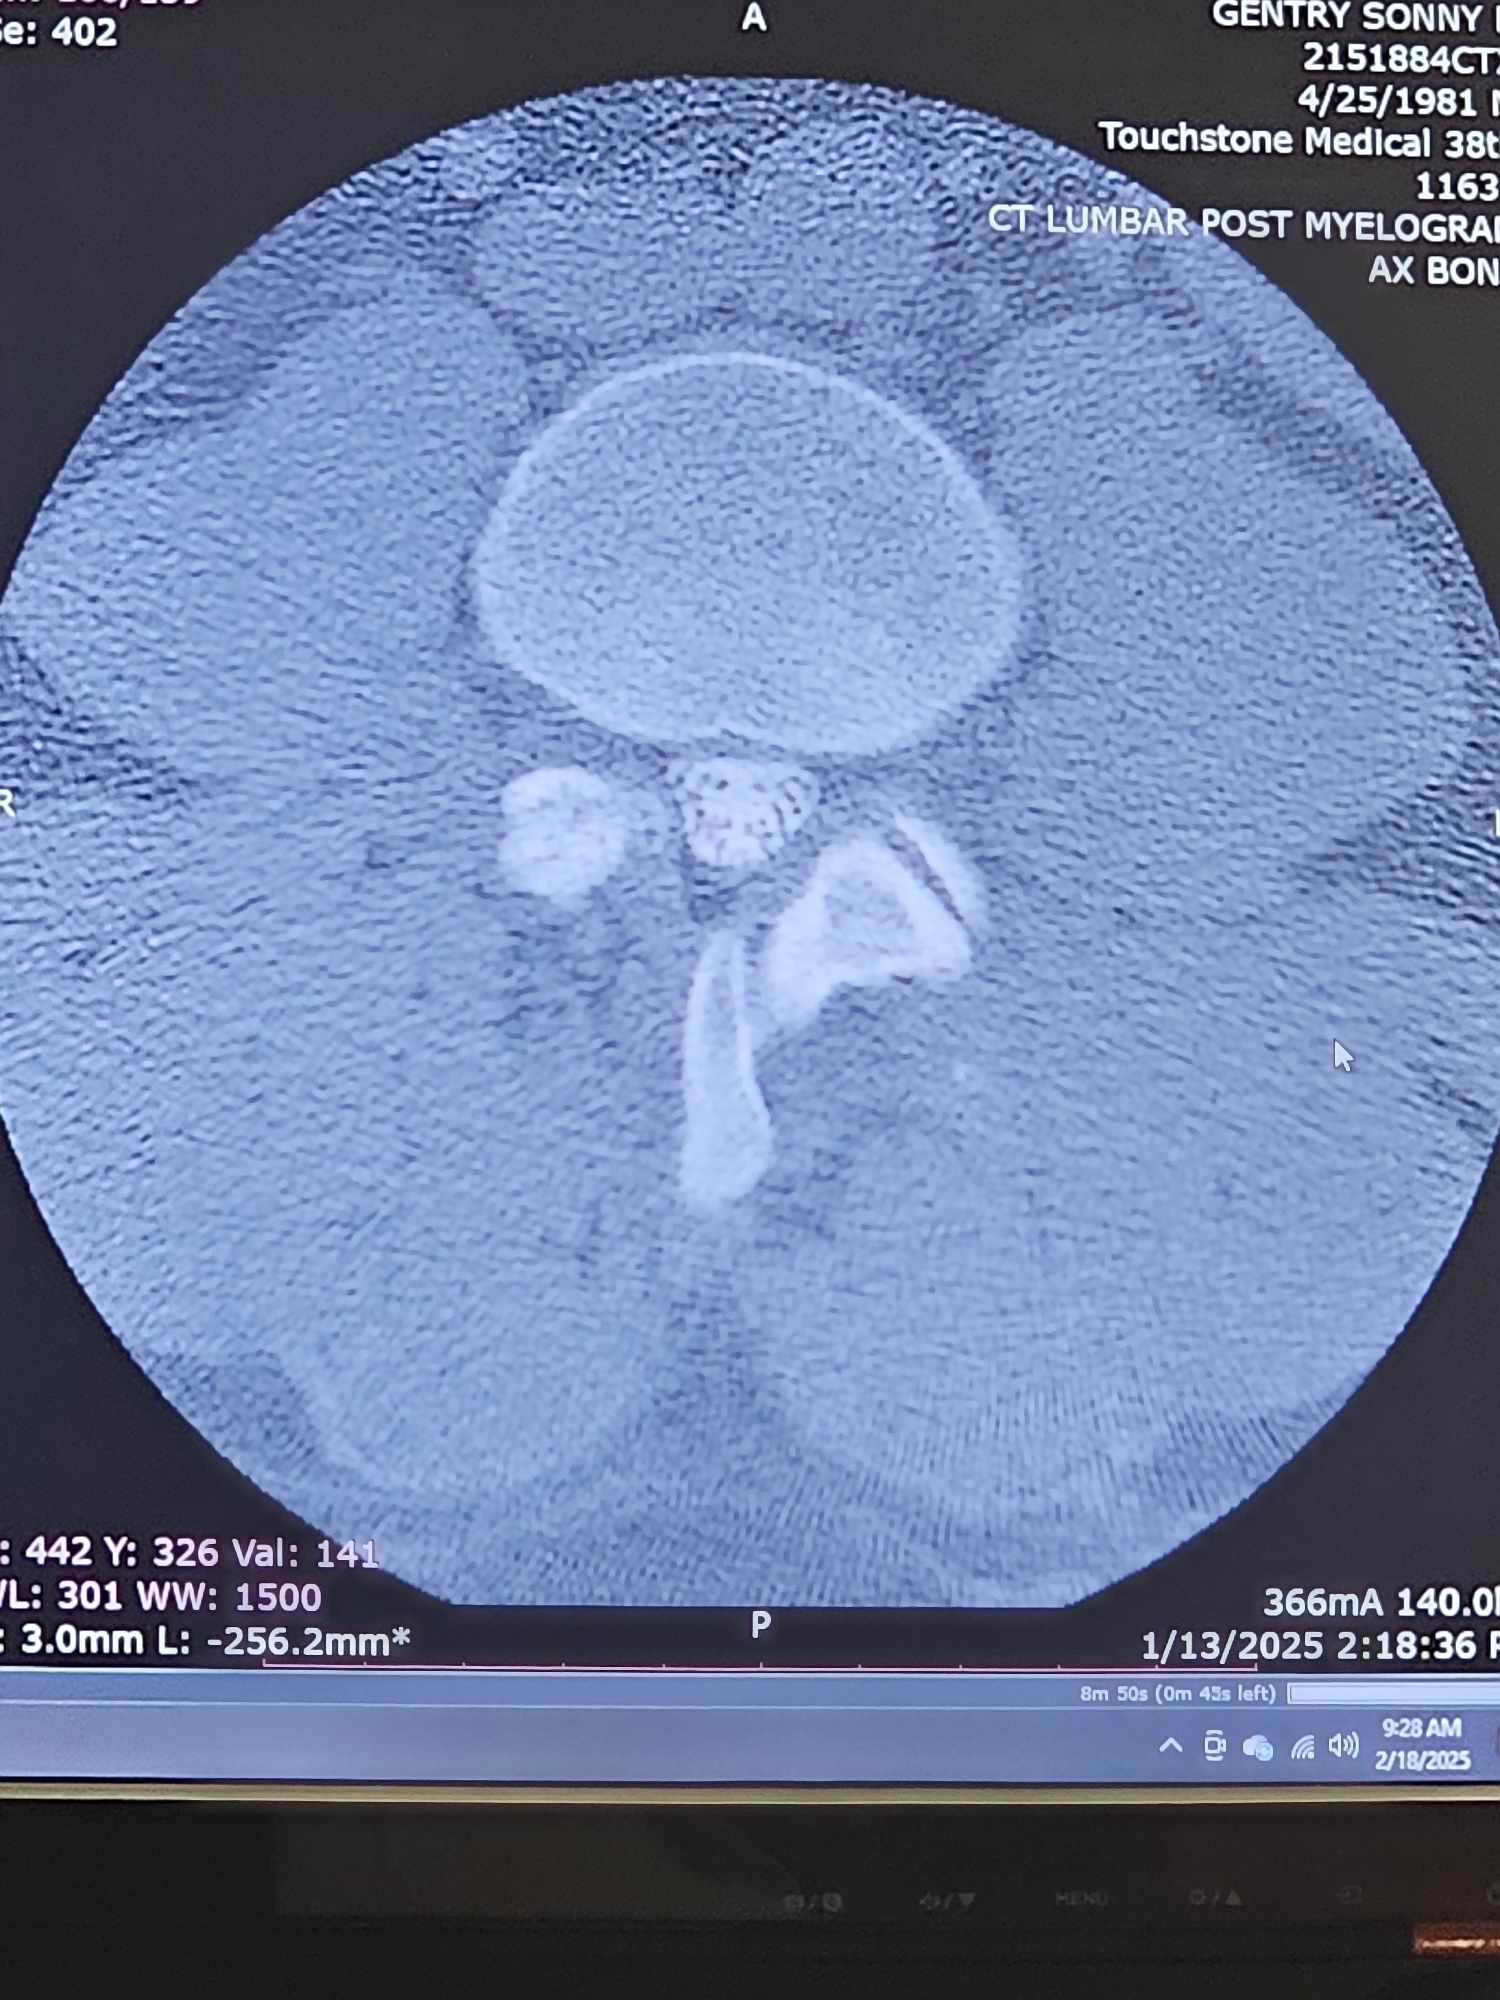

My name is Sonny Gentry. I was in a wreck 3 years ago at no fault of my own at 70 mph. As time passed by, my neck and lower back began to deteriorate. After waiting a very long time, I finally had surgery on July 15th, 2024, and that was a complete fail. I am only able to stand for 30 minutes at a time, and meds only help very little. Just really needing help with bills and meds as I am unable to work after all these years of working. Please feel in your heart to help. If CashApp $southerneuf81 or Venmo @sonny-gentry25 is better for you, then that's great too.